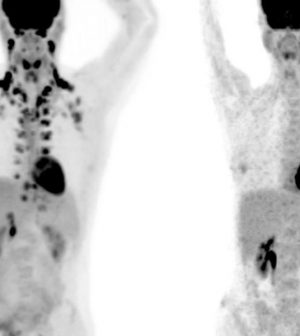

Researchers can detect active brown fat stores using PET scans that are normally used to diagnose and track cancer by looking for tissues burning heavy levels of glucose.

Cohen and his team reached out to Memorial Sloan Kettering Cancer Center, obtaining more than 130,000 PET scans from more than 52,000 patients. They then reviewed those scans to search for brown fat deposits.